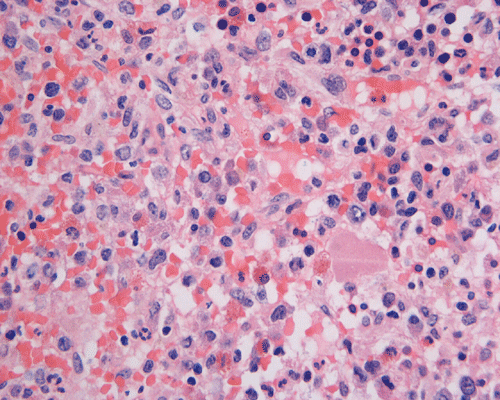

Clinical information The patient was a 73 year-old man with an itchy skin rash, hepatosplenomegaly, and gastrointestinal bleeding.  On admission, his complete blood count (CBC) showed an elevated white count (21,000/cm3) with 25% monocytes and 16% eosinophils, hemoglobin of 9.8 g/dL and 8,000 platelets/cm3.  His 24-hour urine histamine was >200 mg/mL (ref 5.6-13.5 mg/mL). A bone marrow biopsy was performed and the representative photomicrographs are illustrated below:

Normal mast cells have a round or oval, centrally located nucleus with uniform distribution of dark purple granules in the cytoplasm.  Mast cells are well demonstrated by toludine blue and Giemsa stains, and also by immunohistochemistry for CD 117 or tryptase. Napthol ASD chloracetate esterase also highlight mast cells specifically. Mast cells are also positive for CD45, CD33, and CD68 but these markers are less specific than tryptase.  Bone marrow aspirations stained with Giemsa are most useful for recognizing atypia in mast cells. It should, however, note that Giemsa stain may be false negative in formalin fided tissue. Hallmarks of atypia in mast cells include spindling of mast cells, hypogranulation, uneven granule distribution, and nuclear lobulation.  Recognition of the so-called mast cell granuloma, in which mast cell aggregrates are associated with lymphocytes and eosinophils can be helpful.

In the bone marrow, three morphologic patterns of mast cell accumulation have been recognized.  Type I shows focal clusters of mast cells with preservation of bone marrow fat and other hematopoetic elements.  The burden of mast cells is more in Type II and usually shows patchy clusters of mast cell replacing bone marrow in a hypercellular marrow background with osteosclerosis and fibrosis.  Type III is diffuse replacement of the marrow space with mast cells, often with circulating mast cells in peripheral blood.  It is also important to note that mast cells are easily over looked on routine H and E stain or are mistaken for histiocytes.